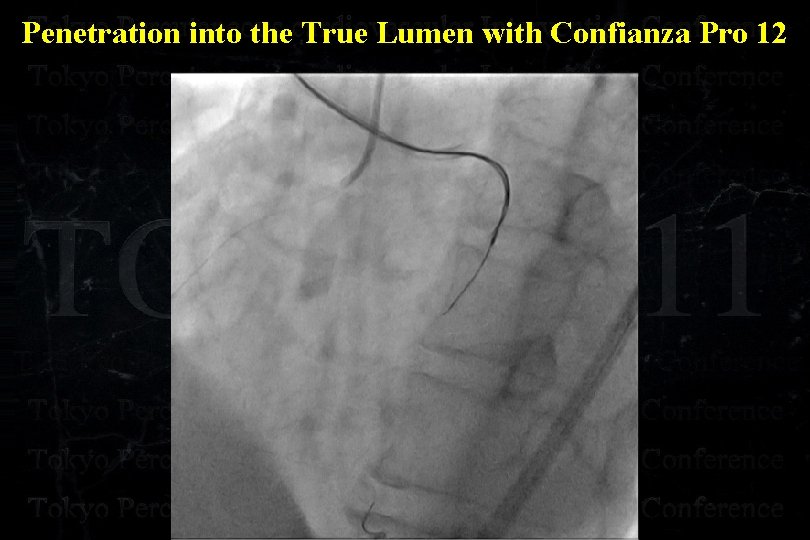

Penetration into the True Lumen with Confianza Pro 12

Penetration into the True Lumen with Confianza Pro 12

Penetration into the True Lumen with Confianza Pro 12